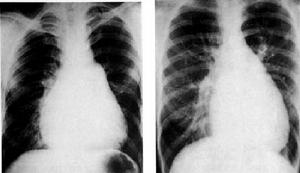

![]() | ![]() |

肛門梳硬結1.2一般資料觀察病例399例均為門診患者,依就診順序奇偶隨機分為2組。治療組200例,男112例,女88例;年齡16~90歲,平均45.2±13.6歲;病程2~45年,平均9.9±2.7年;病性屬中醫辨證血熱淤滯型者170例,環狀混合痔嵌頓水腫無血栓形成者131例;病位在3點位者161例,7點位者157例,11點位者154例,其他點位者39例;兼直腸黏膜鬆弛者72例。對照組199例,男118例,女81例;年齡17~80歲,平均43.3±12.1歲;病程3~41年,平均8.7±2.5年;病性屬中醫辨證血熱淤滯型者163例,環狀混合痔嵌頓水腫無血栓形成者137例;病位在3點位者93例,7點位者157例,11點位者154例,其他點位者38例;兼直腸黏膜鬆弛者62例。2組性別、年齡、病程、病性、病位、兼夾證等經統計學處理,2組比較,差異均無顯著性意義(P>0.05),具有可比性。